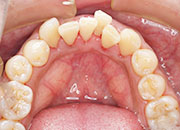

症例1

初診で前歯の保険の差し歯が変色し形も色も悪いのでセラミックで治したいと希望した患者さんです。

術後

患者さんは女性で柔らかい感じにしたいと希望がありましたので少し丸みをだして作りました。患者さんは満足しております。

術後4年経過

タバコを吸う方ですが歯の色の変色や着色また歯肉退縮もなく歯垢の付着もありませんでした。

術前

後前

4年後